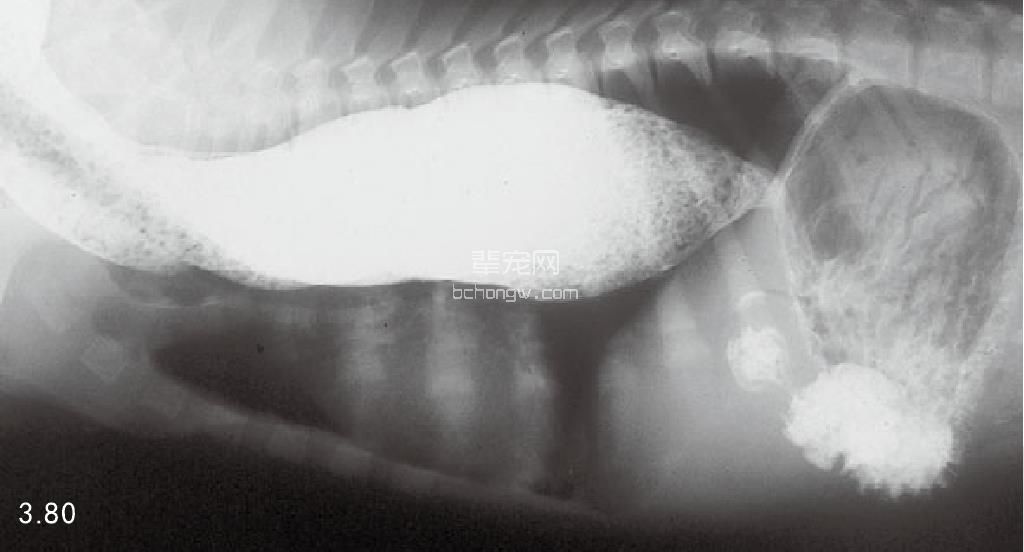

诊断 通过病史和胸腔常规X线片可以诊断 (图3.77~图3.80),但如果需要确定特殊的病 因,则需要进行额外的试验(表3.7)。如果不能 确诊可以做食管X线片和食管镜试验,但通常没有 这个必要(图3.81和图3.82)。德国牧羊犬、大丹 犬、爱尔兰赛特犬、小型雪纳瑞犬和硬毛 易患 先天性巨食管症。犬胃扩张-扭转综合征时,也 可能暂时性继发巨食管症。

图3.80 11岁杂种犬特大的巨食管症与继发性肺叶尖部吸入性肺炎。没有发现神经肌肉或代谢疾病,因此将本病定为特发性巨食管症。